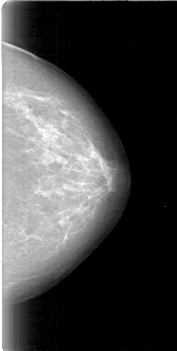

D_4011_1.LEFT_MLO

LEFT_MLO LINES 5386 PIXELS_PER_LINE 2851 BITS_PER_PIXEL 12 RESOLUTION 43.5 NON_OVERLAY

D_4011_1.LEFT_CC

LEFT_CC LINES 5251 PIXELS_PER_LINE 2641 BITS_PER_PIXEL 12 RESOLUTION 43.5 NON_OVERLAY